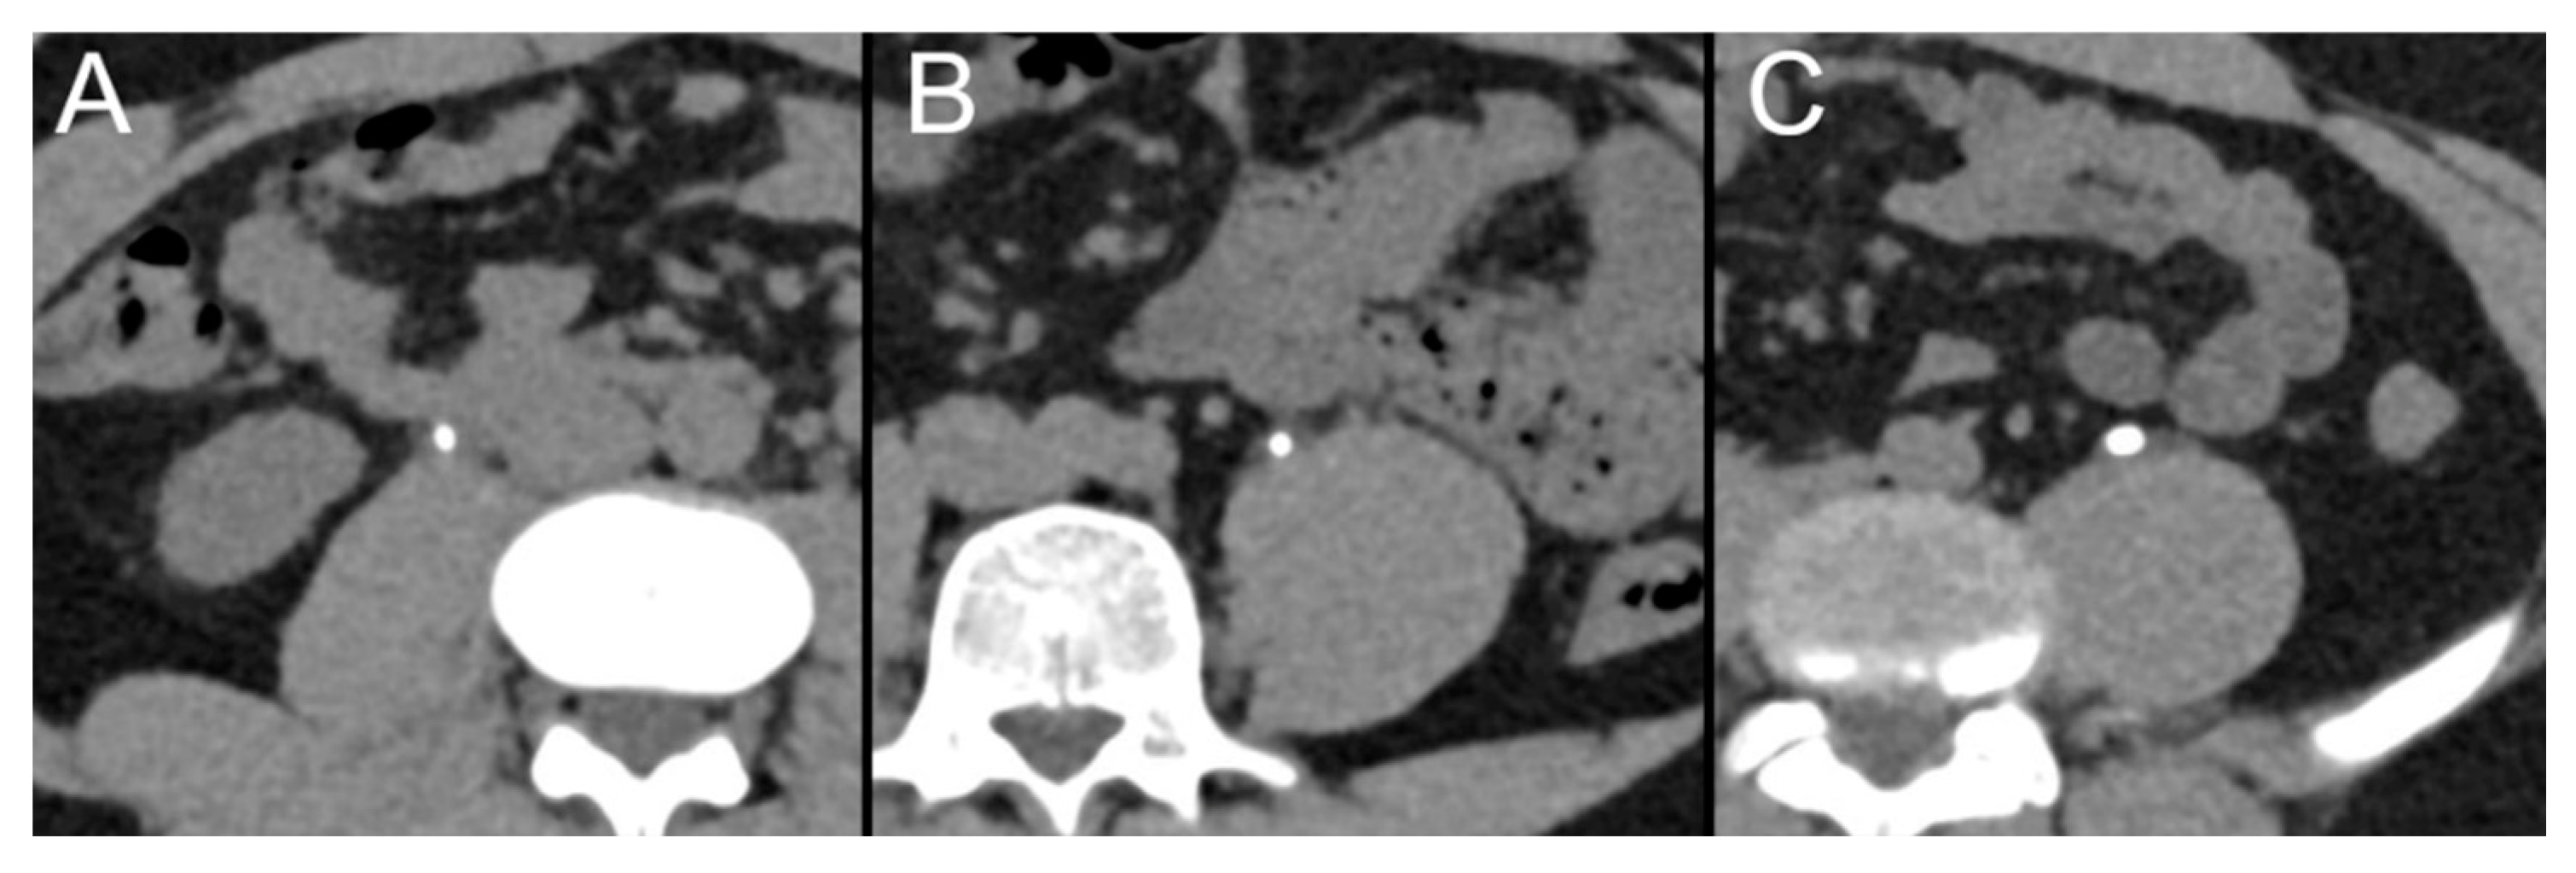

2.6. Stone Size Measurements

3.5. Stone Size Measurements